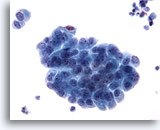

Miction, atypie

En présence de groupes de cellules, un échantillon peut être classé dans la catégorie “atypie”. Ces échantillons sont normaux dans environ 20 % des cas.

60x

Miction, atypie

En présence de groupes de cellules, un échantillon peut être classé dans la catégorie “atypie”. Ces échantillons sont normaux dans environ 20 % des cas.

60x